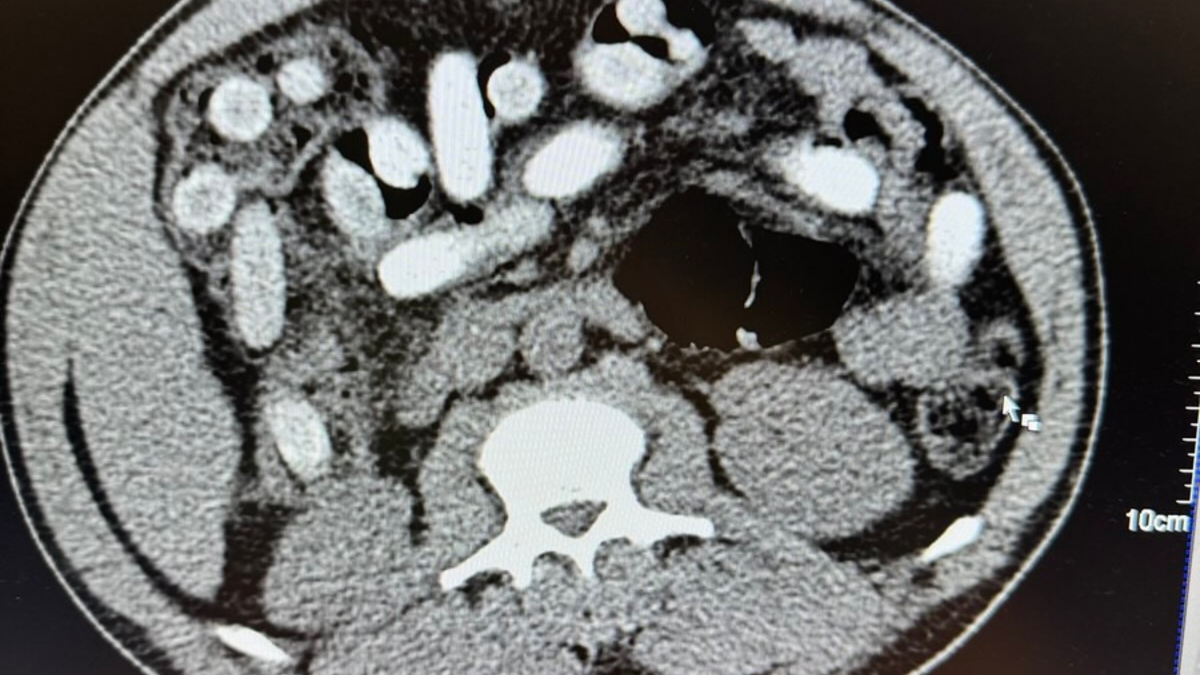

"Die Röntgenaufnahme in einem nahegelegenen Krankenhaus bestätigte letztendlich den Verdacht meiner Kollegen. Der komplette Magen-Darm-Trakt des Mannes war voll mit Drogenpäckchen, sogenannten Bodypacks. In der Größe und Form sind diese mit Datteln vergleichbar. Nach dem Ausscheiden der Drogen war klar, der Mann hatte 111 dieser mit Kokain gefüllten Bodypacks geschluckt. Rund 1,3 Kilogramm Kokain versteckt im Körper ist für uns ein neuer trauriger Rekord. Das Risiko beim Körperschmuggel ist enorm. Wenn nur ein Päckchen im Körper aufgeht, ist das Leben des Mannes nicht mehr zu retten, selbst wenn ein Arzt direkt danebensteht", so Jens Ahland, Pressesprecher des Hauptzollamts Köln.